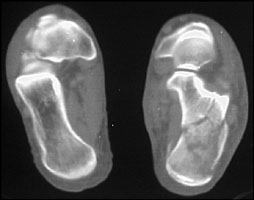

- Click on the image for a larger versionCAxial CT. This image of both feet shows a calcaneal fracture. The normal size is included for comparison.